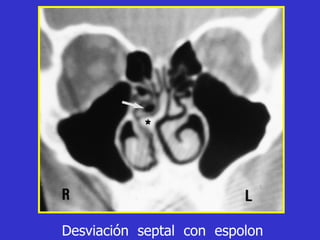

Este documento describe las diferentes proyecciones radiográficas utilizadas para examinar los senos paranasales, incluyendo las proyecciones básicas de Caldwell, Waters lateral y las proyecciones especiales como Hirtz y Waters mentonasal. También describe las diferentes estructuras anatómicas que componen el complejo ostiomeatal anterior y posterior de los senos paranasales.